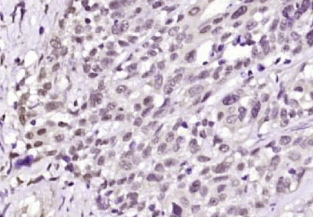

多聚甲醛固定,石蜡包埋(人结肠癌);用柠檬酸钠缓冲液(pH6.0)煮沸15min后获得抗原;用3%过氧化氢阻断内源过氧化物酶20分钟;阻断缓冲液(正常山羊血清)37℃30min;抗体(ACK1)多克隆抗体在1:200孵育。在4°C下过夜,然后根据SP试剂盒(兔子)说明和DAB染色进行操作。